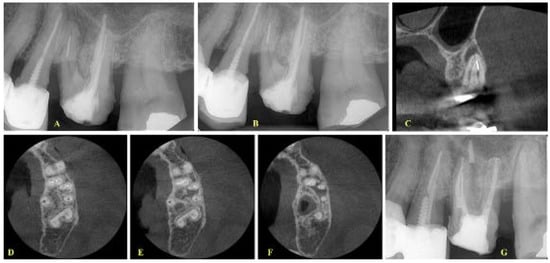

- In cases where the canals were merging, then a final treatment plan of leaving the fragment in situ was set, irrespective of the presence or absence of lesions (Figure 3 and Figure 4). The only occasion that would induce a modification to this treatment plan (i.e., leave the fragment in situ) was to conclude, after CBCT assessment and evaluation of canal curvature, that the removal of the fragment located at the middle level of the root would not be of a high difficulty degree procedure (Figure 5).